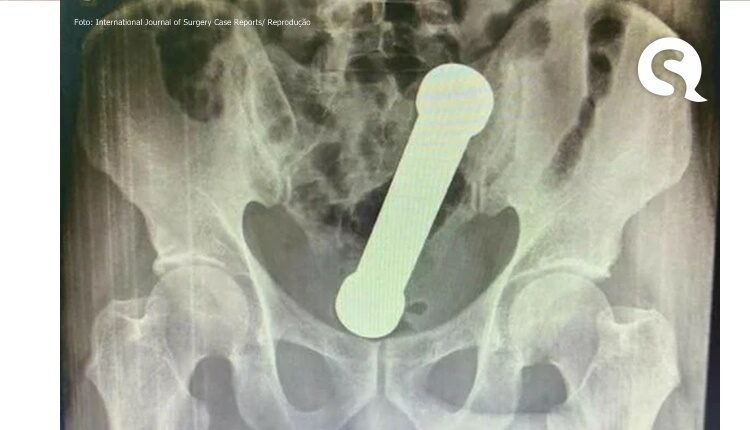

Ao realizarem um exame de raio-X, os médicos encontraram um peso de dois quilos, de cerca de 20 centímetros de comprimento, como os que são usados em academias de ginástica para exercícios de braço, dentro do homem.

O haltere estava entre o reto e o intestino grosso do paciente, que, depois do exame, admitiu ter introduzido o peso de academia no corpo para obter satisfação sexual.